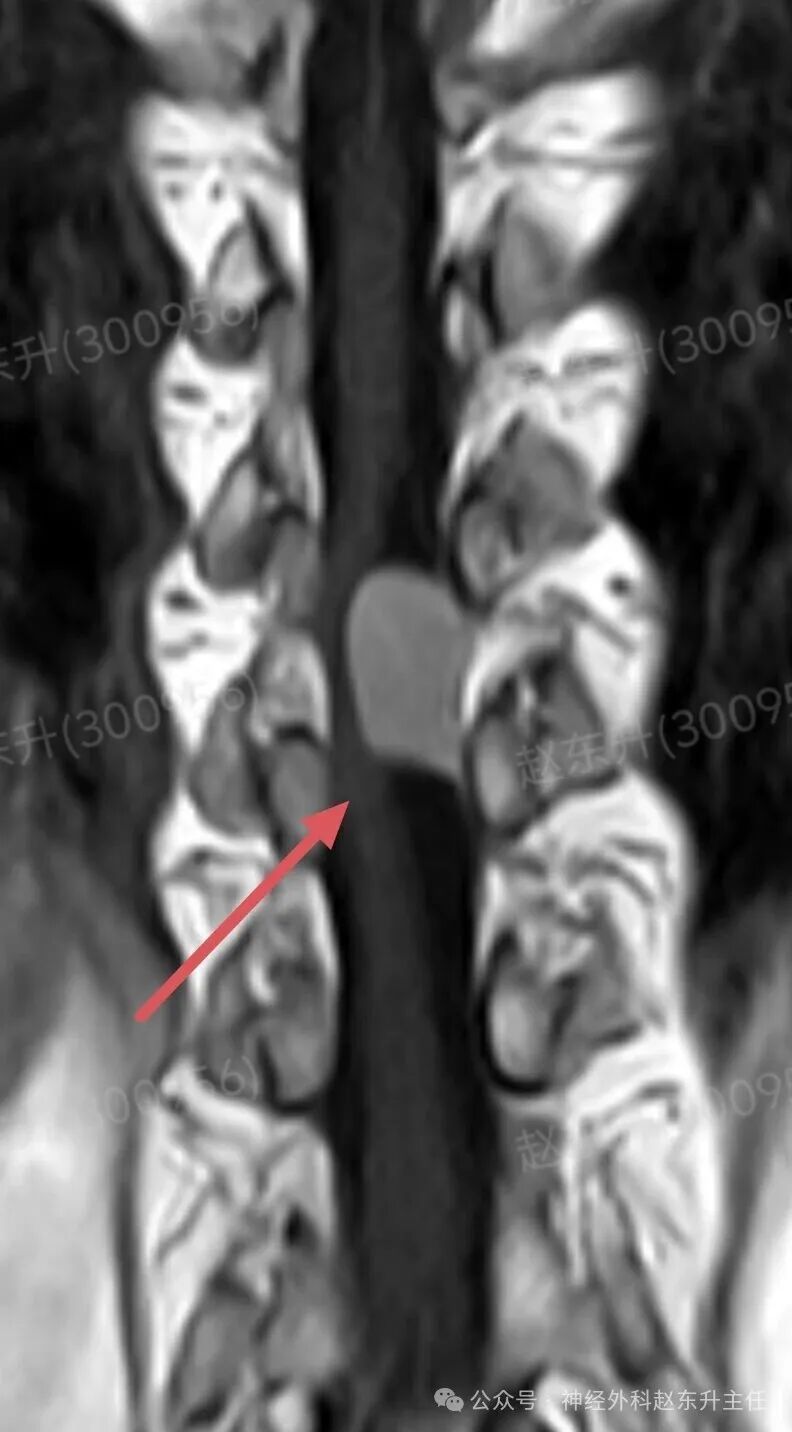

有一天门诊来了一位69岁的甘肃女性患者。因为长期腰腿疼,在多家医院就诊治疗无效,长期按摩针灸拔罐艾灸电疗磁疗腰腿疼,稍有缓解。随后又持续加重,在外院查腰椎磁共振,未见明显异常,随后在向上查胸椎磁共振,发现椎管内一个巨大肿瘤压迫脊髓比较明显。她疼痛评分有6分,夜间疼痛难忍,难以入睡。此次发现椎管肿瘤以后来到我院就医。根据胸椎磁共振的表现,考虑脊膜瘤可能。随后在全麻下,我们在显微镜下彻底切除了肿瘤组织术后患者疼痛缓解下地行走,较术前改善大小便也恢复正常了。

图片图片图片图片图片图片肌电图提示下肢神经、骶神经损伤术中切除的肿瘤组织西安市红会医院神经外科赵东升主任介绍:椎管内脊膜瘤是一种常见的、通常为良性的椎管内肿瘤,起源于覆盖脊髓和神经根的脊膜(特别是蛛网膜的“帽细胞”)。核心特征:性质:绝大多数(90%以上)为良性(WHO I级),生长缓慢。位置:可发生于椎管的任何节段,但最常见于胸椎(约占70%),其次是颈椎、腰椎少见。特点:肿瘤通常有完整的包膜,与硬脊膜基底紧密相连,像一颗“附着在墙壁上的珍珠”,可压迫脊髓和神经根,但通常不侵入神经组织本身。发病率:是椎管内最常见的肿瘤之一,约占所有椎管肿瘤的25%。好发于中年女性(女:男比例约为4:1),可能与激素水平有关。

病史与神经系统查体:医生通过询问病史和详细的神经系统检查,初步判断病变的节段和严重程度。影像学检查(确诊的关键):增强磁共振(MRI): 是诊断的金标准。典型表现:T1加权像上呈等或稍低信号,T2加权像上呈等或稍高信号;增强扫描后呈现显著的、均匀的强化。特征性的“硬脊膜尾征”(肿瘤附着处硬脊膜线状强化)具有重要诊断价值。可清晰显示肿瘤与脊髓、神经根的关系。CT扫描:可显示肿瘤是否伴有钙化(沙粒体型脊膜瘤常见),以及是否有椎体或椎弓根的骨质增生,但对软组织分辨率不如MRI。X线平片:作用有限,可能仅见椎弓根间距增宽等间接征象。